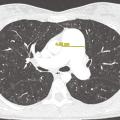

L’hypertension pulmonaire (HTP) associée aux maladies respiratoires chroniques est fréquente chez les patients présentant une bronchopneumopathie chronique obstructive (BPCO) avec ou sans emphysème, une pneumopathie interstitielle diffuse (PID), un syndrome emphysème-fibrose ou encore une hypoventilation alvéolaire. Ces HTP…